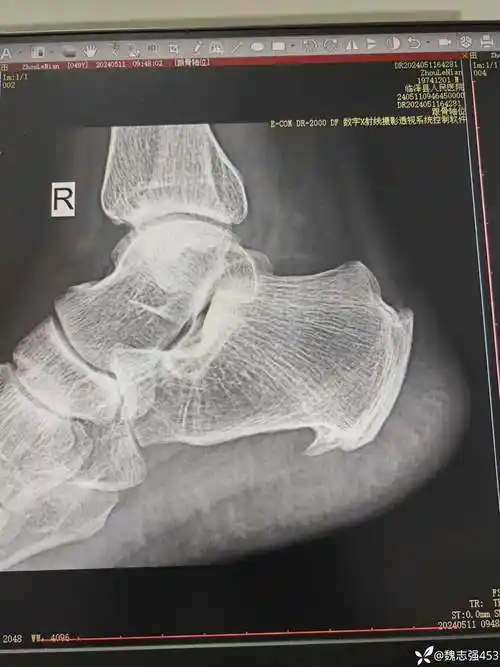

跟骨骨刺该怎么办?

跟骨骨刺

顽固性足跟痛-跟骨骨刺-手术治疗 - 好大夫在线